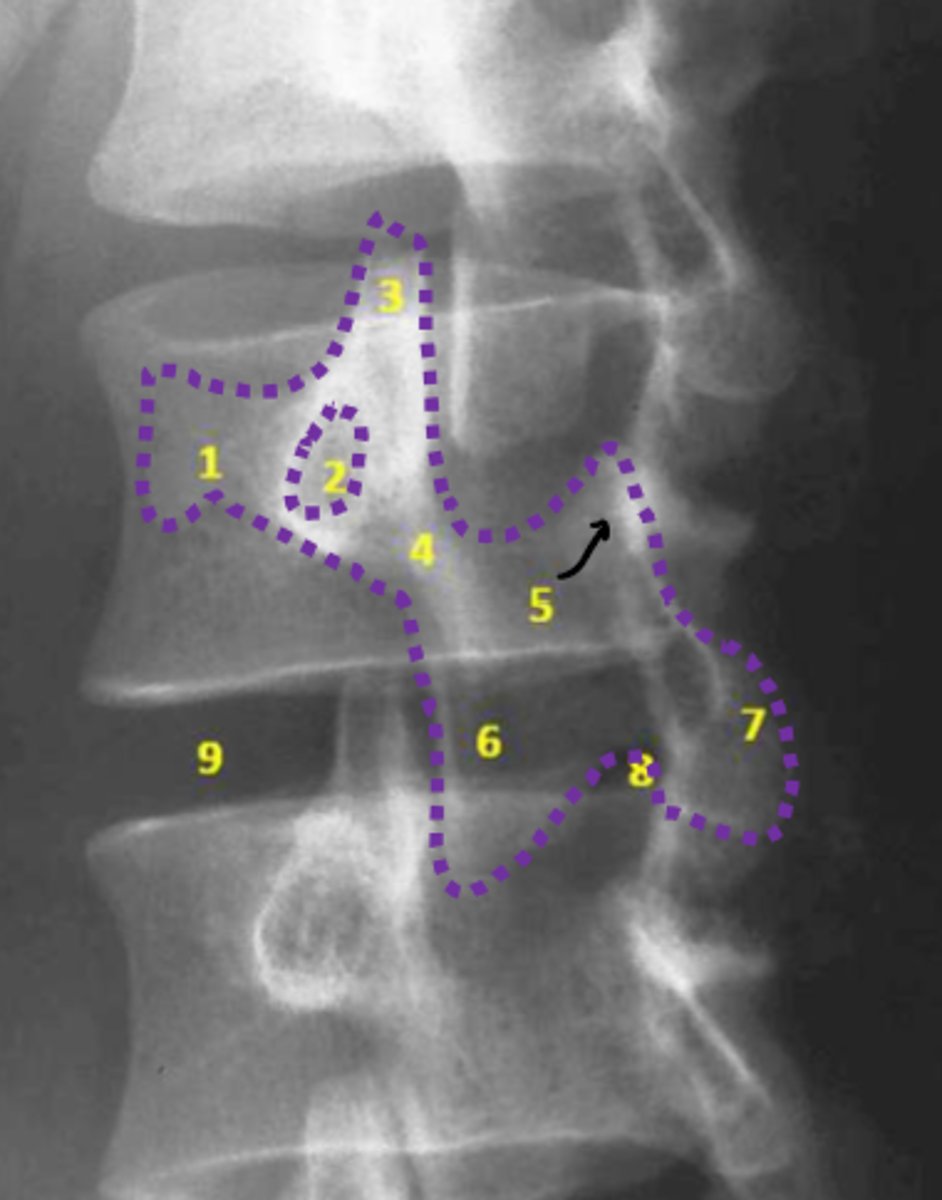

lumbar

What vertebrae is being examined?

lumbar vertebral body

Identify the blue structure

pedicles

Identify the green structure

transverse processes

Identify the purple structure

spinous processes

Identify the yellow structure

joint space between superior and inferior articulating facets

Identify the red line

intervertebral foramen

Identify the orange structure

pedicles

Identify the green structure

spondylolysis

pars interarticularis

oblique view

What condition is being examined for in this radiograph?

What structure is it looking for?

What view is this radiograph in?